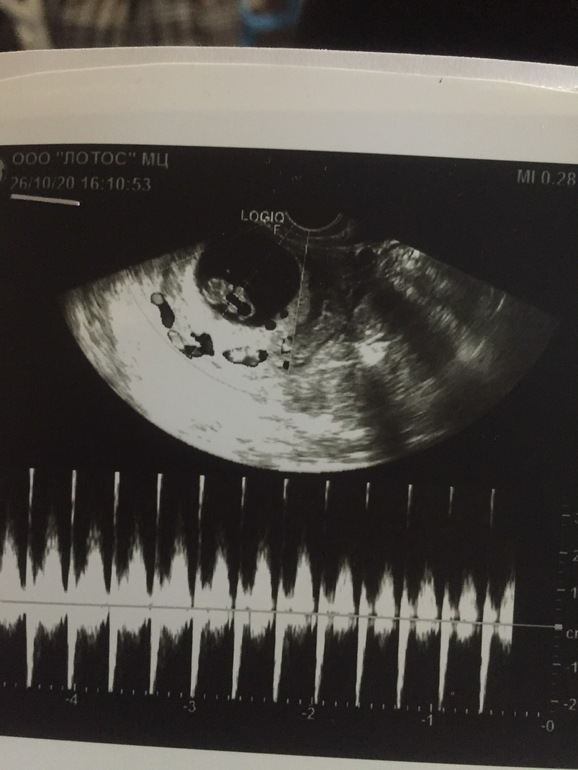

УЗИ 8-9нед

Девочки что то я не понимаю почему плохо видно карапуза?((( или по узи все нормально ?

На пустом месте проблему придумали 🤦🏼♀️ «Плохо видно»? Ну это же узи! Это не фотография. Он есть там, живой, сердце стучит, нет надо до чего-то докопаться) вам нельзя нервничать